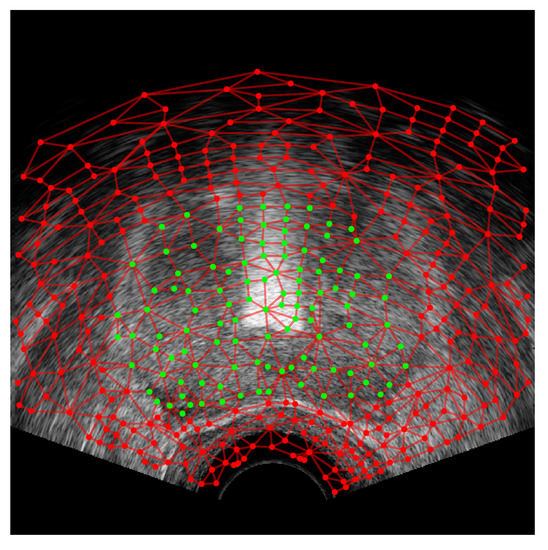

where the corresponds to the graph-cut procedure, and the optimization is carried out through a pattern search algorithm. Once the optimal centre point has been found, with a minimal labelling cost across all of the slices, the prostate segmentation is complete, as shown in Figure 10. All regions labelled with after graph cutting are inside of the prostate, which could be represented in a binary image where all of the pixels inside of the regions have a value of one and all other pixels are zero. To smooth out the segmented prostate contour, the contour model is fit to the pixels on the perimeter of the binary region . The perimeter pixels are transformed to the contour model coordinate system using (50), and then the model is fit to these pixel points from the least-squares fitting given in (6), thus creating a 3D contour model for the segmented prostate; see Figure 11. The results of the segmentation on a number of patient image sets is given in Section 6.

Figure 10.

Superpixel regions after graph-cut procedure. The centroids of regions labelled as being inside of the prostate, , are displayed with green dots, and the centroids of the superpixel regions outside of the prostate, , are displayed with red dots.